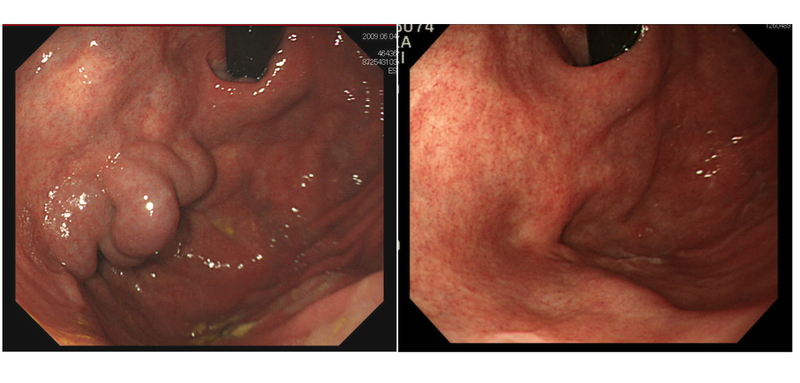

静脈瘤に対してはおもに内視鏡治療を行いますが、胃静脈瘤に対してはバルーン閉塞下逆行性経静脈的塞栓術(B-RTO)というカテーテル治療が有効な症例もあります。

慢性の肝疾患、とくに肝硬変と診断された患者さんは、ぜひ“門亢症”を念頭に置いて定期的な検査(超音波・内視鏡・CTが三種の神器)を受けてください。また、メタボリック症候群(通称、メタボ)の心当たりがある方も「隠れ肝硬変、隠れ門亢症」かもしれません。ぜひ一度、検診を受けてみることをお勧めします。